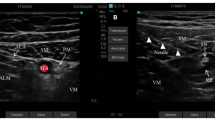

An ultrasound guided ABPB was then performed. The patient was placed in the supine position with the upper limb abducted on the surgical side. The elbow joint was flexed at 90°, exposing the armpit. A bedside ultrasound instrument (Venue 50, GE Medical Systems (China) Co., Ltd) was used with a high-frequency linear array probe (L8-18i, GE Medical Systems (China) Co., Ltd) in nerve block mode. The ultrasound probe was placed in the armpit, and the axillary artery was scanned along its short axis. The axillary artery was centred on the screen, and the locations of the three nerves around the axillary artery were determined. The median nerve is usually located at the 9–12 o’clock position of the axillary artery, the ulnar nerve is usually located at the 2 o’clock position, and the radial nerve is usually located at the 5 o’clock position8. Local anaesthetics were injected near the nerves innervating the skin of the incision. If the surgical area extended beyond the area innervated by a nerve, a single-point injection was still performed, and the anaesthesiologist selected the nerve to be injected. The needle was inserted from the outside of the probe, and the needle tip was placed near the axillary artery and the target nerve. A small amount of saline (not more than 0.5 ml) was injected to ensure that the needle tip was in an ideal position. Next, a set volume of 0.2% ropivacaine was injected. The ultrasound images before and after injection are shown in Fig. 1.